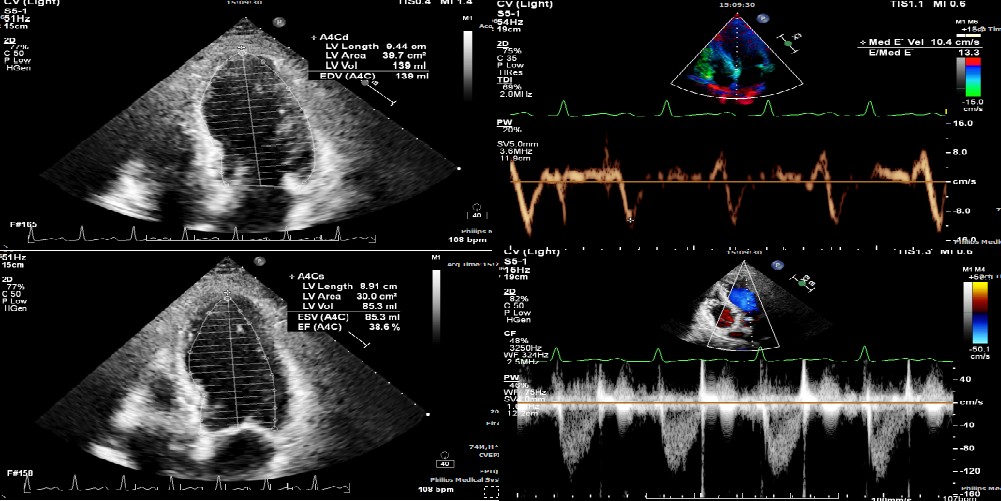

Relevant Test Results Prior to Catheterization

Theseries tests were provided on him prior to catheterization including laboratorytest, chest X-ray, and echocardiography. Mild elevation of cardiac enzymes andmild pulmonary edema were presented. The echocardiography showed 35% of leftventricular ejection fraction with hypokinesia of left ventricular basalinferior wall, apex, and mid-to-apical anterior wall. The rest of tests were unremarkable.